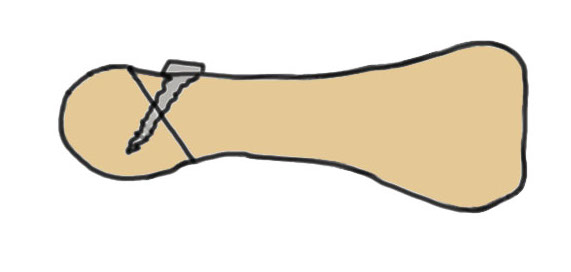

Dorsal closing wedge osteotomy

Concept

Most affected portion is dorsal

Redirects plantar articular surface

Results

Pereira et al Foot Ankle Int 2016

- 20 patients treated with osteotomy

- mean follow up 23 years

- 80% excellent, 20% good results